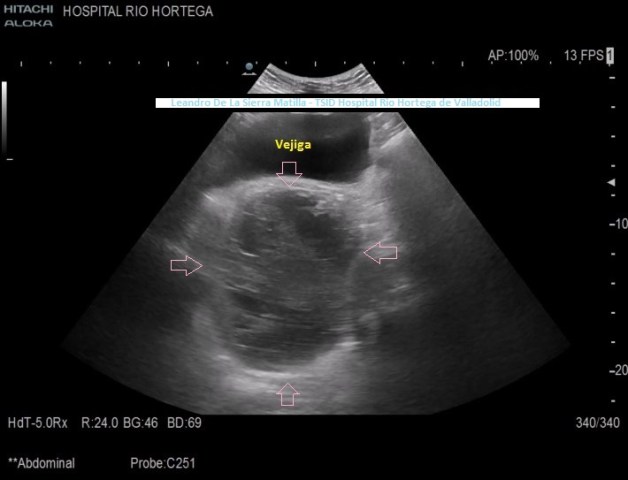

Presentamos el caso de una mujer de 83 años de edad que acude a la consulta de ecografía remitido por su médico de familia por un aumento del volumen abdominal de pocos meses de evolución, sin ningún otro síntoma.

Se realiza estudio de Ecografía Abdominal protocolizado, en el que se observan entre otros hallazgos, varias lesiones esplénicas y ováricas (flechas rosas) junto con una mínima cantidad de líquido libre abdominal.(FIG 1,2 y 3)

1

2

3